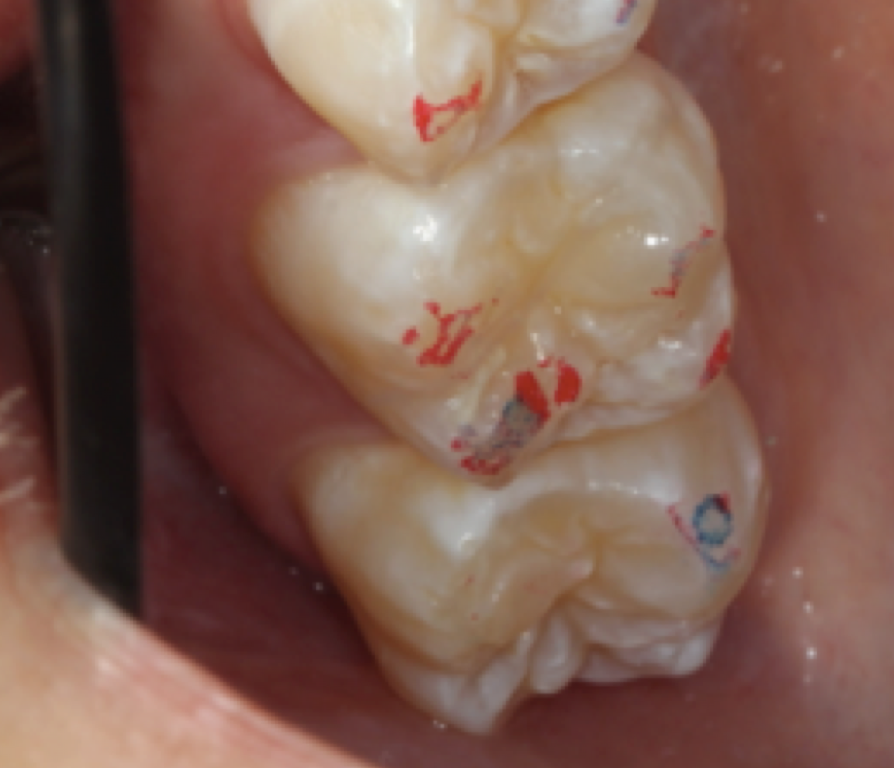

After centric relation is found, the point of first contact must be determined. The point of first contact may be a keystone tooth, but not everyone has a keystone tooth. The point of first contact needs to be marked, but not necessarily physically. In Figure 1, showing teeth Nos. 2 and 3, the point of first contact is on the mesiolingual cusp of No. 2, which has the strongest blue mark. There is also a slight mark on the distal buccal cusp of tooth No. 3. When the jaw is in centric relation, the point or coincident points of first contact are called centric occlusion. Centric relation is a joint position and is found independent of tooth contact; the joint is centered and teeth do not need to touch if centric relation is in the joint space. When the opposing teeth come together in the joint space, the term is centric occlusion.1

MIP is the term for the habitual bite, when the patient squeezes together and the maximum number of teeth touch. Centric occlusion can be determined with bilateral manipulation, bilateral guidance (Figure 2), or a leaf gauge (Figure 3).6 The position may or may not coincide with MIP.7,8 If the dentist is planning to restore the tooth that has the point of first contact, the existence or absence of a slide must be determined. The author's preferred technique to identify the slide is by having the patient squeeze the teeth together in MIP to determine whether the jaw shifts in any substantial way when going into that position.

The clinician next transitions from load testing to looking inside the mouth. Attrition, fremitus, and fractures are evaluated intraorally. A comprehensive occlusal examination seeks out the point of first contact as well as interferences. Understanding the patient's excursive and posterior interferences can be useful in determining attrition, fremitus, and fractures. These interferences are revealed with two different colors of articulating ribbon or paper.15,16 The dentist uses the light color first, instructing the patient to move "left, right, forward, back," to "chew it" or "break the paper," and to move "everywhere, further than you think you can." Most patients will clench while they are following these instructions, which limits the normal range of motion they would have in a chewing or bruxing stroke. There is no magic bullet to help a dentist to resolve this other than patience. After having the patient move in all previously stated directions in one color, the patient should tap together two or three times in MIP in the darker color. The lighter color lines and smudges will show where excursive movements and interferences are, and the darker dots will indicate the MIP contacts. This is important for the ultimate comfort of the patient's restoration, but it does not have much to do with TMJ issues. Although the common assumption is that teeth do not have any bearing on what happens with the jaw joint, it is still important to know details related to interferences regarding restorative dentistry and longevity of the periodontium. Another way to do this is with T-scan technology.15,16

Fig 1. Point of first contact.

Figure 1